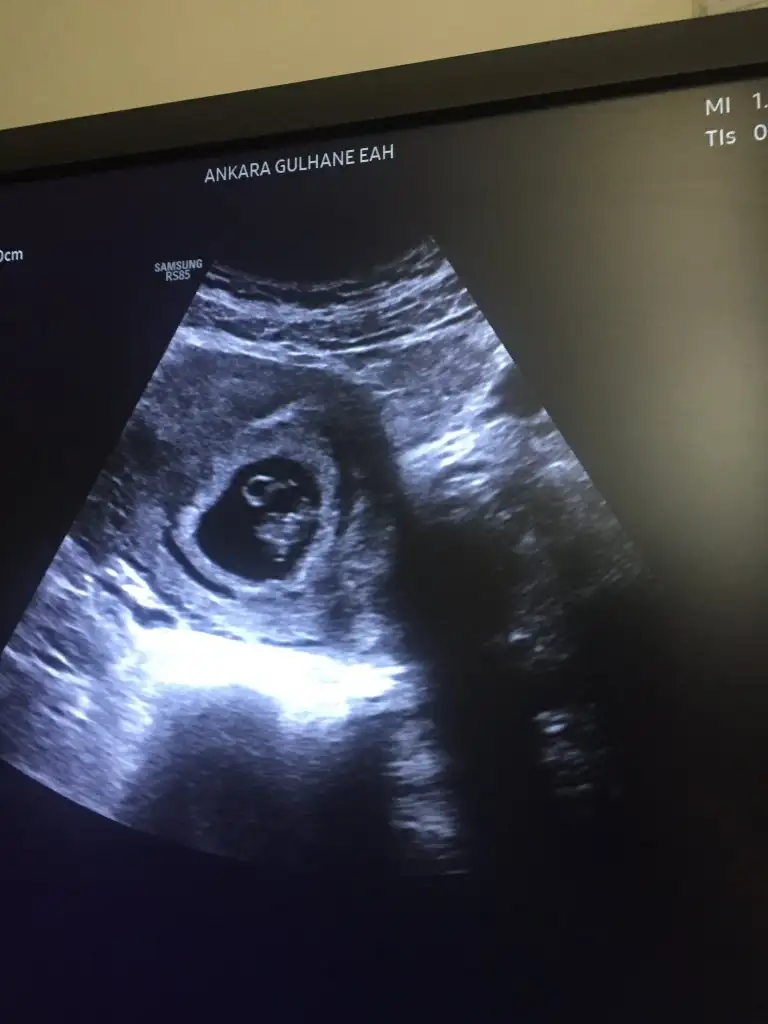

Yok canım takma kafana benim Bebek 6+5 iken gözükmedi sadece biraz büyümeye ihtiyacı var merak etme Pazartesi gitçez tekrar bakalım aşırı heyecanlıyım 8+1 olcaz inşallah hem görürüz hemde kalp atışını duyarız sende merak etme zamanı gelince görünür

Oh şükür duydum kalp atışını herşey normal dedi doktor minişimin Fotoğrafınıda ekliyorum